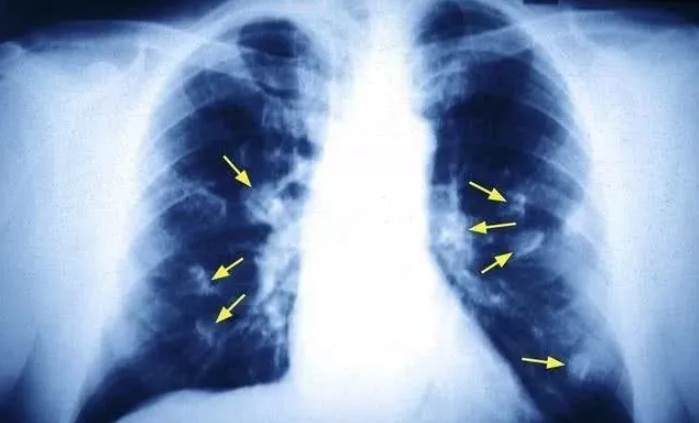

根據《大參考》報導,這名男童因連續咳嗽不止,被家人帶往醫院檢查,X光結果發現肺部有腫瘤,確診為早期肺癌。醫師驚訝于年紀這麼小就罹癌,進一步詢問才得知,男童的父親每天抽菸高達1至2包,且在家毫不避諱,讓家人長期暴露于二手菸環境中。

醫師指出,兒童正處于生長發育階段,細胞及基因不斷分裂,若長期吸入二手菸,極容易發生基因突變,增加罹癌風險。